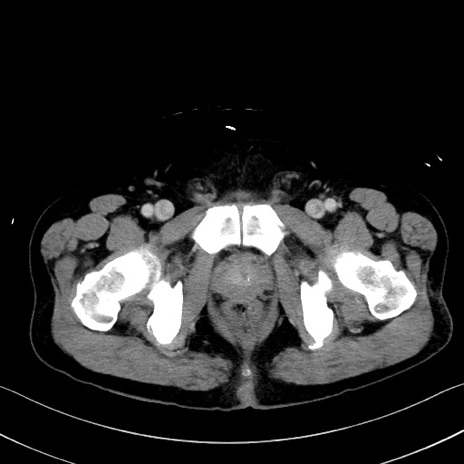

症例35(横断像)

【症例】70歳代 男性

【主訴】腹部膨満、嘔吐

【現病歴】昨日より腹部膨満感出現。本日増悪し、仙痛出現。嘔吐あり、受診。

【既往歴】糖尿病、胆摘後

【身体所見】BP 149/80mmHg、HR 74/min、BT 35.9℃、腹部:膨満、軟、圧痛なし。腸雑音減弱あり。上腹部正中切開瘢痕あり。

【データ】WBC 13500、CRP 1.72